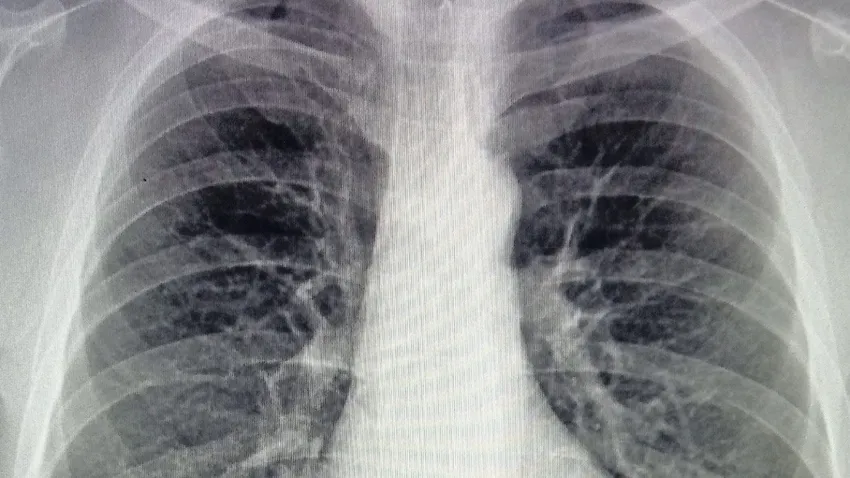

4110_cancer-pulmon

El gen MET codifica una proteína clave en la señalización y crecimiento celular. Cuando está mutado, puede favorecer el desarrollo del cáncer. Este tipo específico, el cáncer de pulmón de célula pequeña, representa aproximadamente el 15 % de todos los tumores pulmonares y tiene una supervivencia a tres años de apenas el 15 %. Su diagnóstico suele ser tardío y la progresión muy rápida, lo que limita las opciones de cirugía.